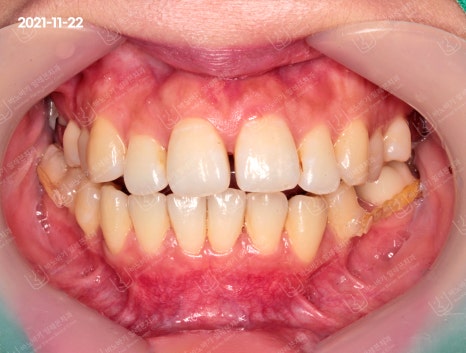

치아 사진을 촬영해보았는데요. 윗니와 아랫니가 생각보다는 깊이 물린 것 같진 않았습니다.

다만 상악 전치 4개의 배열이 불규칙한 것으로 나타났습니다. 하악 치열도 비뚤어져 있었고, 이로 인해 중심선이 어긋나서 불일치하는 경향을 보였습니다.

측면 교합도 살펴보았습니다. 앞니가 앞으로 크게 기울어져 입을 도드라져 보이게 만드는 핵심적인 원인으로 작용했네요.

게다가 어금니(제2소구치) 또한 탈락한 것으로 확인되었습니다. 돌출입 교정 시에 이런 부분을 종합하여 계획을 수립했습니다.